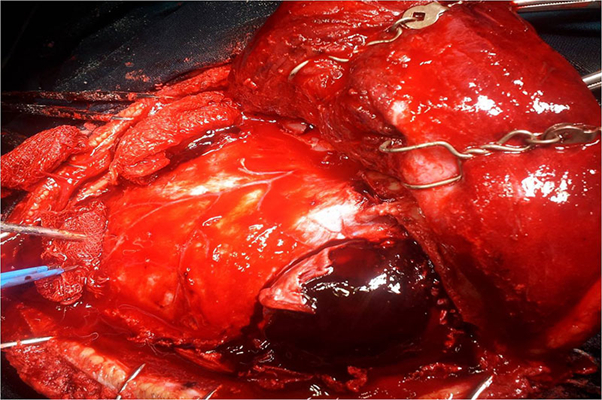

顱內血腫圖片

硬膜下血腫 (45)

硬膜下血腫 (46)

硬膜下血腫 (47)